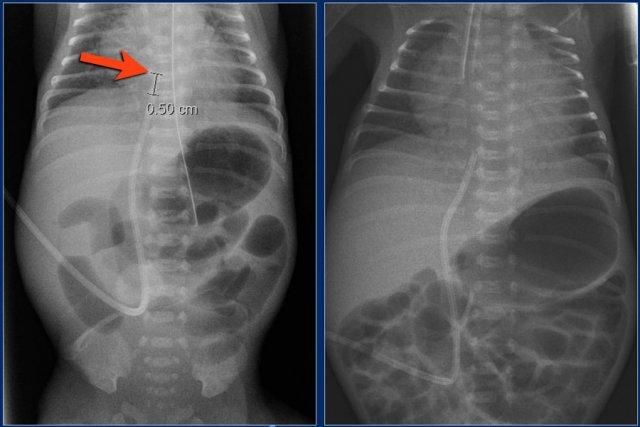

Các phát hiện bao gồm:

- Đặt sai vị trí đường truyền động mạch rốn, bị gấp khúc trong lòng động mạch chủ bụng.

Đường truyền động mạch rốn (4)